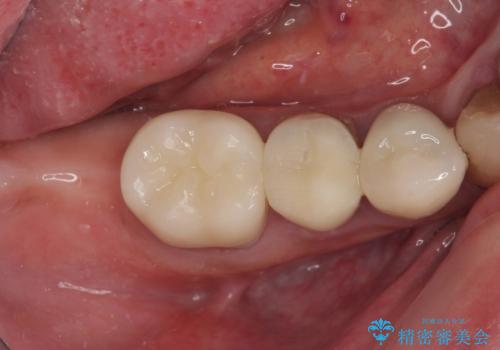

奥歯がしみる オールセラミッククラウンによる奥歯のむし歯治療